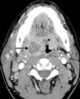

Peritonsillar abscess

Peritonsillar abscess (PTA), also known as quinsy, is an accumulation of pus due to an infection behind the tonsil. Symptoms include fever, throat pain, trouble opening the mouth, and a change to the voice. [Source: Wikipedia ]